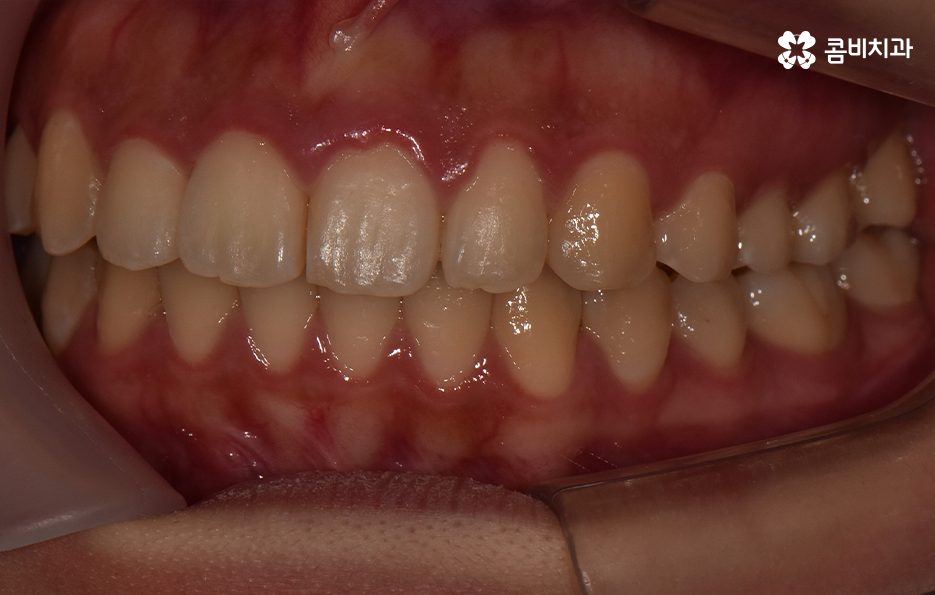

덧니는 윗니와 아랫니에 모두 있거나 앞니에 살짝 있는 수준의 덧니도 있으며 덧니가 심한 경우에는 개방교합으로 인해 입이 잘 다물어지지 않는 경우도 있기 때문에 덧니가 심한 정도에 따라서 치아교정의 계획은 세부적으로 달라질 수 있어요

덧니가 심하지 않은 경우에는 비발치로도 충분히 교정을 하는 경우도 있겠지만 덧니가 심한 경우에는 덧니 발치 교정을 통해서 치료가 진행되는 경우가 많이 있는데요. 그 이유는 치아교정의 원리를 생각하더라도 치아를 재배치하기 위해서는 기존의 치아가 움직일 공간이 필요한데 덧니는 치열이 이미 완성되고 있는 상태에서 치아가 나올 공간이 부족하여 덧니가 되는 경우가 많다는 점에서도 치아의 이동 공간을 확보하기 위한 발치가 필요할 수 있는 거예요

물론 치아의 이동 공간을 조금만 확보하면 되는 경우에는 악궁 확장이나 치간 삭제와 같은 방법으로도 치아의 이동 공간을 확보하여 비발치로 치아교정이 가능한 사례도 있지만 덧니 교정을 통해서 부정교합과 함께 얼굴형의 변화까지 치료 목적으로 하는 경우에는 발치가 필요한 경우가 많다고 볼 수 있어요